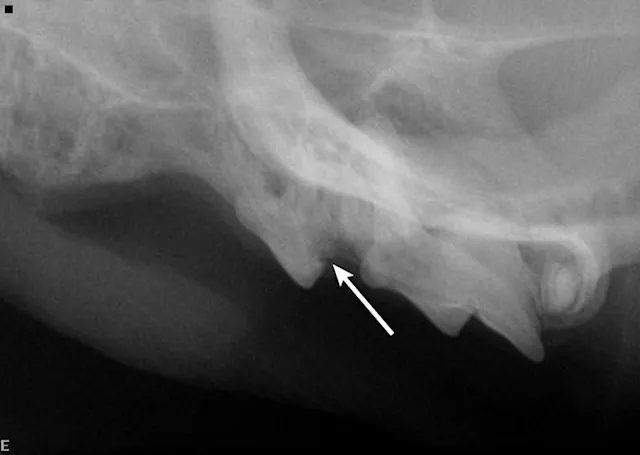

FIGURE 1

Intraoral image of the left maxillary canine revealing inflammation and a tooth fragment (arrow) extending into the oral cavity

A complete oral examination and full-mouth dental radiographs were performed with the patient anesthetized. The detailed oral examination confirmed unhealed extraction sites with sharp crown fragments protruding from the alveoli into the oral cavity. In addition, an advanced TR lesion was noted affecting the left maxillary third premolar tooth (Figure 3). Dental radiographs confirmed advanced type 2 resorption affecting all involved teeth, as well as oral extension of the remaining tooth structure (Figure 4).